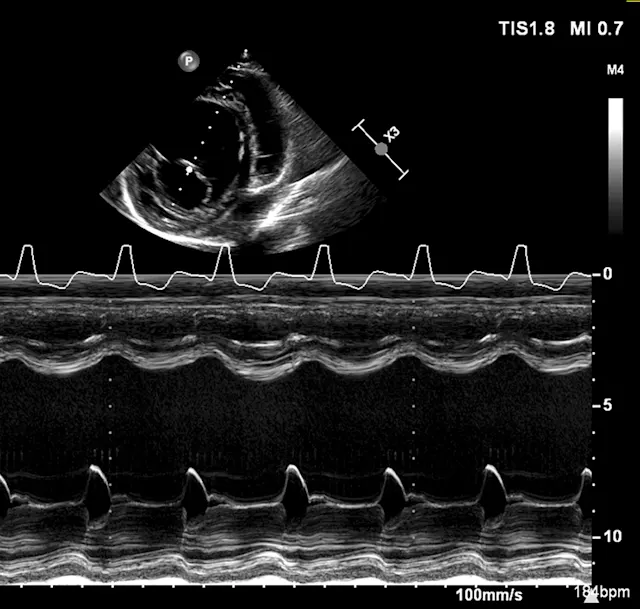

An echocardiogram and thoracic radiographs were obtained. The echocardiogram revealed decreased left ventricular (LV) wall thickness, severe dilation of the LV chamber (ie, eccentric hypertrophy), and severely reduced LV systolic function. Severe left atrial enlargement with a moderate degree of centrally directed left atrioventricular valve regurgitation (suspected functional) was observed. The left atrioventricular valve leaflets appeared normal in thickness with poor coaptation due to annular stretch. In addition, there was mild dilation of the right atrium and ventricle with a mild degree of right atrioventricular valve regurgitation. Results of echocardiography were consistent with dilated cardiomyopathy (DCM; Figures 1-4).2,3

Figure 1

2D echocardiographic image of the left ventricle from the right parasternal short axis view. There is decreased thickness of the LV walls and severe dilation of the LV cavity consistent with DCM.